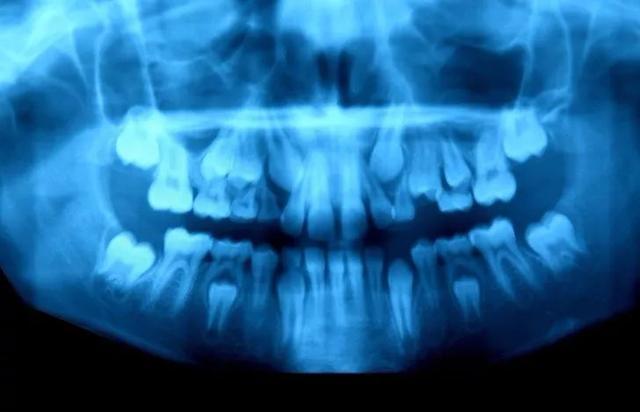

小孩子乳牙被恒牙取代下颚,看起来有点惊悚!

“多齿症”患者的X光照片